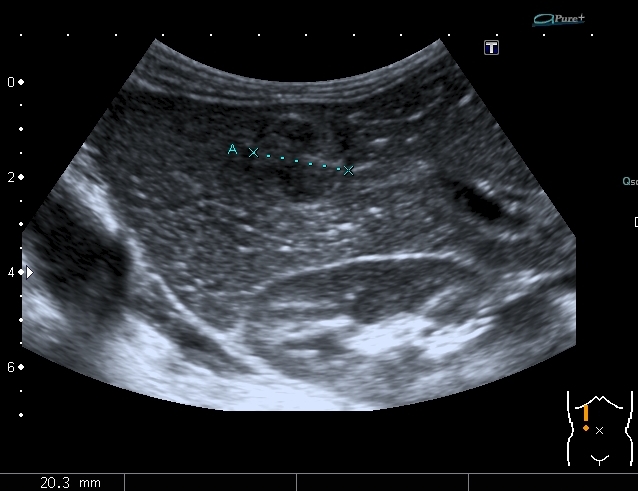

Добавляю сканы печени, я думаю они являются хорошей подсказкой о природе изменений в лёгких

Добавляю источник изменений в легких, печени и забрюшинном пространстве

Всё левое подреберье было выполнено опухолевым конгломератом, источником его я предположил левую почку, хотя разобраться , где почка, селезёнка, а тем более надпочечник я не смог.